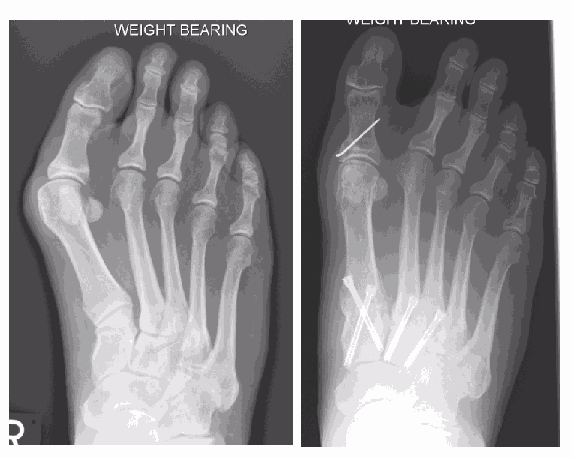

Metatarsus adductus surgery normally involves realignment by fusing the medial midfoot joints. In a paper published by the department the outcomes following surgery on 59 patients were examined.

The conclusion following the investigation was that this procedure is very effective in correcting the deformity with a significant improvement in patient reported outcome measures one-year post procedure. Complications were noted with removal of the fixation in nine cases, stiffness of the big toe joint in three patients and one patient having one joint that failed to fuse, although no further treatment was required as it was not painful.

This X-ray shows a significant bunion (hallux valgus) only. The first metatarsal (a) in isolation has drifted away from the second (b)

This X-ray shows a bunion, however the metatarsus adductus angle is significant, reflecting the medial drift of the first three metatarsals towards the inside of the foot. Now the bunion cannot be corrected by just addressing the first metatarsal alone.

The far X-ray shows the bunion and metatarsus adductus angles having been successfully addressed by fusion the medial three metatarsals with screw fixation.